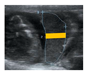

3.3. Doppler Ultrasound

In guinea pigs from G25 until term, UA PI was examined and described as a quadratic negative nonlinear regression (Figure 3A), whereas MCA PI was detected from G35 until G65 and fitted to linear regression (Figure 3B). Both PI measures decreased across pregnancy. We found that CPR fitted to a quadratic nonlinear regression but with a high variability (r2 = 0.2030) (Figure 3C). Lastly, UtA PI showed a straight-line fit with a high variability across gestation (r2 = 0.1004) (Figure 3D).

Figure 3.

Doppler ultrasound across pregnancy. Guinea pig pulsatility index of (A) umbilical artery (UA), (B) middle cerebral artery (MCA), (C) cerebroplacental ratio (CPR), and (D) uterine artery (UtA) pulsatility index, and their best fit from gestational day 25 to the end of pregnancy. Each dot represents an individual measurement (n = 47 from 19 litters). Black line = data best fit. Magenta dashed lines = 95%CI.